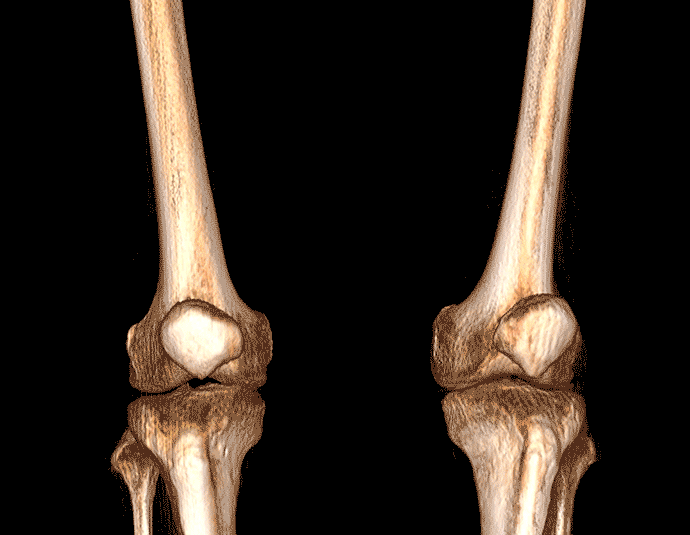

膝关节

VR体绘制重建